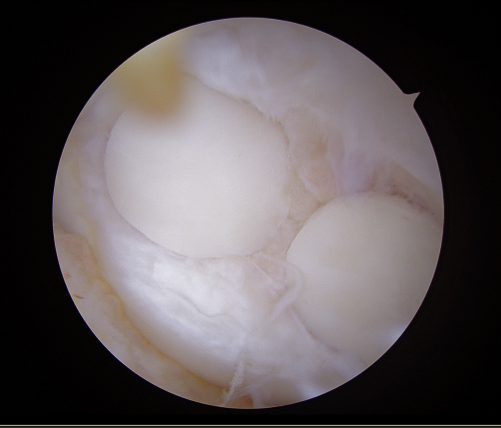

▶수술 후_관절내시경 사진 01

▶수술 후_관절내시경 사진 02

5. 수술 후 결과 — “연골은 잘 살아있습니다”

수술 후 경과 관찰에서 중요한 포인트는 세 가지였습니다.

①수술 부위 감염 여부

②연골 이식 부위의 안정성

③무릎 기능 회복 가능성

MRI 및 임상 경과상, 골연골 이식 부위는 잘 유지 되고 있었고, 반월상연골판 역시 봉합 상태가 양호 했습니다.

정렬 또한 목표에 도달한 것을 확인했습니다.